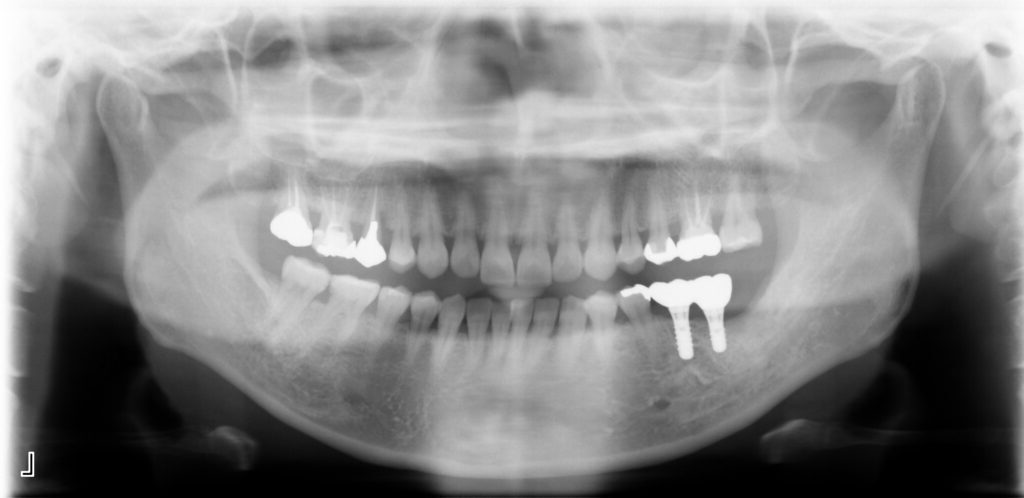

Before

After

治療内容

インプラント2本・骨造成併用

治療期間・回数

約4ヶ月・約4回

費用

880,000円

治療のリスク

外科手術が必要になるため、患者様に体力的な負担がかかる。